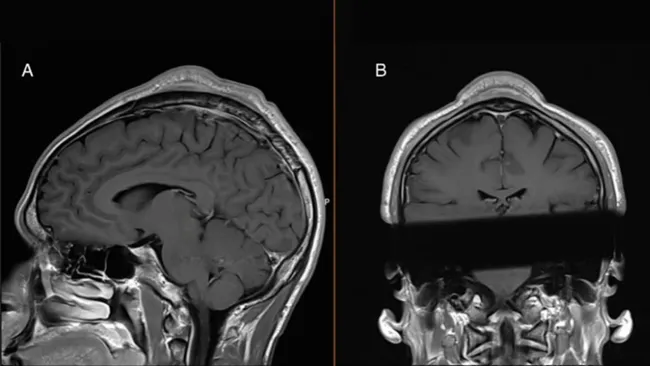

Après avoir consulté, les médecins ont décidé d’intervenir chirurgicalement pour retirer la bosse. Cette opération a permis de retirer la masse de tissu excédentaire située entre la peau et le crâne. De plus, ils ont dû raser une partie de l’os épaissi afin de restaurer son épaisseur normale. Grâce à cette intervention, la bosse a disparu et le patient a retrouvé une apparence normale.

Dans le cas de cet homme, la pression répétée a entraîné un épaississement du tissu sous-cutané ainsi qu’une augmentation de l’épaisseur de l’os du crâne. Cette blessure par surutilisation n’est pas unique à la danse.